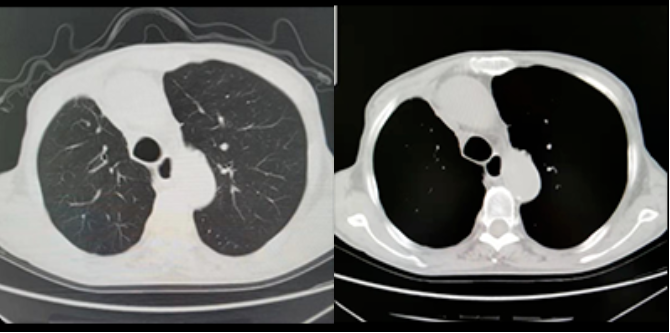

2022年1月胸部CT(图5):

右肺中叶切除术后,未见明显肿瘤复发征像;

右侧少量胸腔积液较前吸收;

右肺慢性炎症较前相仿;

双肺少许感染已吸收;

左肺下叶间裂处小结节同前,建议随访;

脂肪肝,肝脏小囊肿;

胃癌术后改变。

图5.胸部CT影像